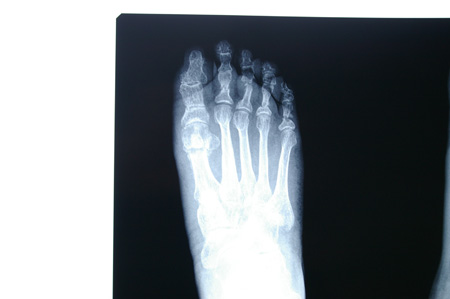

Radiografia post-operatòria